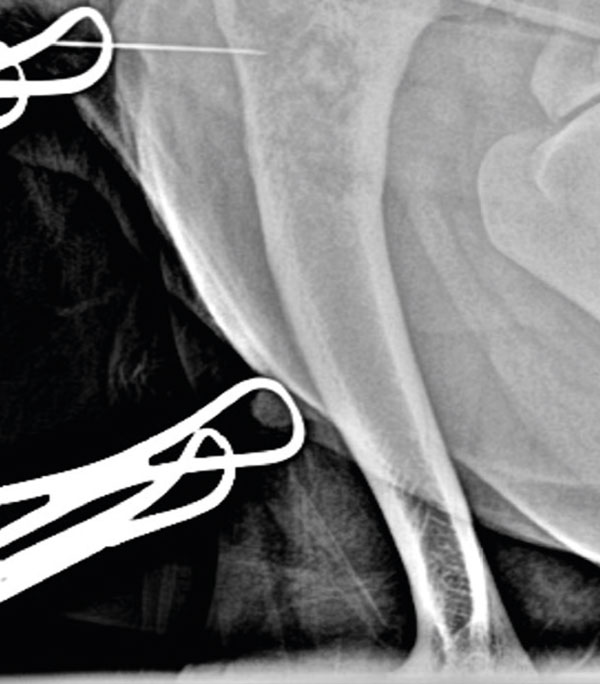

A cranio-lateral approach to the left proximal humerus was performed; an approximately 4cm skin incision was made, and blunt soft tissue dissection allowed exposure of the lateral aspect of the proximal humeral cortex. A 23Gx1 ¼" hypodermic needle was placed in the area of the bone lesion (Figure 2) and x-rays were taken to confirm correct positioning of the needle (Figure 3).

Figure 2.

Figure 3.